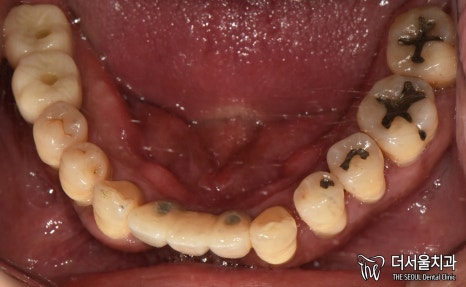

먼저 사진을 보겠습니다.

여러분이 보더라도

구강 상태가 심각하다는 걸 알 수 있습니다.

올바른 교합이 이뤄질 수 없을 뿐더러

치경부 마모증에 쌓여있는 치석에 충치까지

손댈 부분이 너무 많네요.

게다가 구취까지 나고 있었기에

걱정되는 상황이었습니다.

교합면을 확인했을 때도 마찬가집니다.

인접면에 있는 충치와

누워있는 사랑니까지 찾아볼 수 있었습니다.

단기간 내에 끝낼 수 없는 케이스죠.